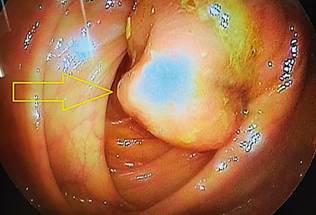

In this context, the general surgery service evaluated the patient and suggested a total colonoscopy. It showed a raised, sessile, mamelonated, subepithelial lesion of approximately 6 cm in diameter at the right colon level near the cecum, which occupied one-third of the lumen of the colon (Figure 3).